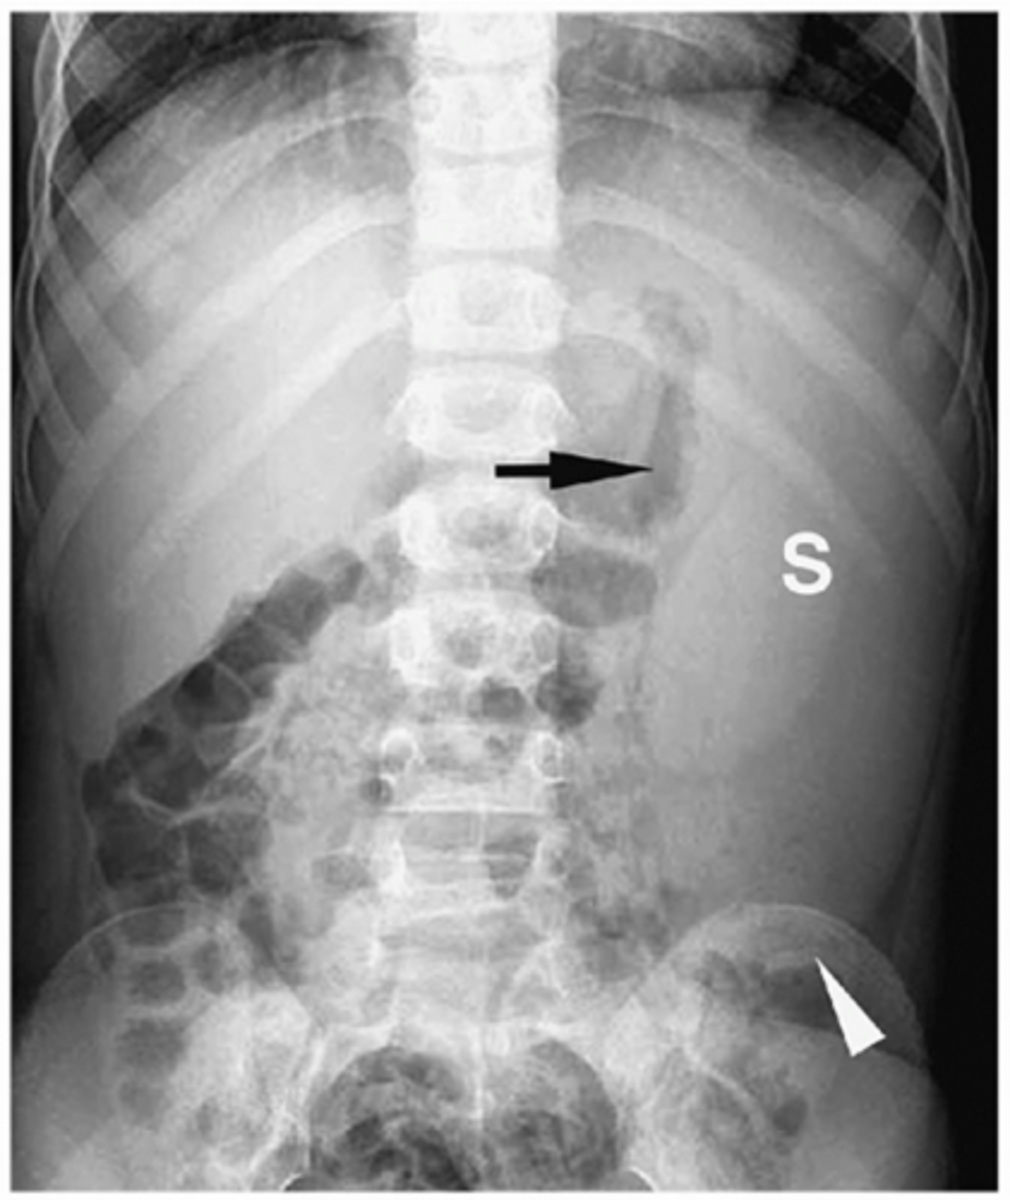

Large bowel obstruction

lesion obstructs lumen of the large bowel, proximal to transition point large bowel dilates, distal to transition point peristalsis continues, emptying colon

Causes: tumor, hernia, volvulus, diverticulitis, intussusception

sigmoid volvulus

dilated sigmoid colon, air and stool in more proximal descending colon

can lead to strangulation (vascular compromise leading to infarction of bowel wall)